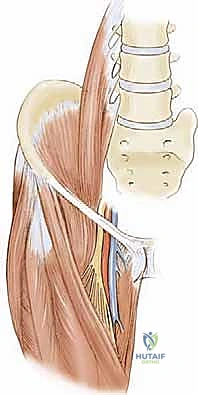

نظرة تشريحية عميقة: كيف تعمل عضلات الورك؟

لفهم طبيعة تشنجات الورك، يجب أولاً فهم التشريح المعقد للمنطقة. مفصل الورك هو مفصل كروي حقي (Ball-and-Socket Joint) يعتمد على توازن دقيق بين مجموعات عضلية متعددة لضمان الاستقرار والحركة السلسة.

1. العضلة الحرقفية القطنية (Iliopsoas Muscle)

هي العضلة الرئيسية المسؤولة عن "انثناء الورك" (Hip Flexion)، أي رفع الفخذ باتجاه البطن. تتكون من جزأين: العضلة الحرقفية والعضلة القطنية الكبيرة. عندما تتشنج هذه العضلة وتقصر، يصبح الطفل غير قادر على فرد فخذه بالكامل، مما يجعله يمشي بوضعية الانحناء للأمام (Crouch Gait) أو يواجه صعوبة بالغة في الاستلقاء بشكل مسطح على ظهره.

2. العضلات المقربة (Adductor Muscles)

تقع هذه العضلات في الجزء الداخلي من الفخذ، ووظيفتها الأساسية هي "تقريب" الساقين نحو خط الوسط للجسم (Adduction). في حالات الشلل الدماغي، يؤدي التشنج الشديد في هذه العضلات إلى تقاطع الساقين أثناء المشي، وهو ما يُعرف بـ "مشية المقص" (Scissoring Gait). هذا التقاطع المستمر لا يعيق المشي فحسب، بل يولد قوى غير طبيعية تدفع رأس عظمة الفخذ تدريجيًا خارج تجويف الحوض.

2. إطالة العضلة الحرقفية القطنية (Iliopsoas Lengthening)

يتم الوصول إلى وتر العضلة الحرقفية القطنية إما من خلال نفس الشق المستخدم للعضلات المقربة، أو عبر شق صغير منفصل في الجزء الأمامي من الورك. يقوم الجراح بقطع الجزء الوتري من العضلة (Tenotomy) مع ترك الألياف العضلية سليمة. هذا يسمح للعضلة بالتمدد دون أن تفقد وظيفتها الأساسية تمامًا.

النتيجة الفورية: يتمكن الطفل من فرد فخذه بالكامل، مما يصحح وضعية الانحناء للأمام.

تقنيات متقدمة لضمان الأمان

يستخدم الأستاذ الدكتور محمد هطيف تقنيات ميكروسكوبية وأدوات دقيقة لضمان عدم المساس بالأعصاب والأوعية الدموية الهامة المجاورة (مثل العصب السدادي - Obturator Nerve). هذا المستوى من الدقة هو ما يميز الجراح الخبير ويضمن تعافيًا أسرع وأكثر أمانًا للطفل.